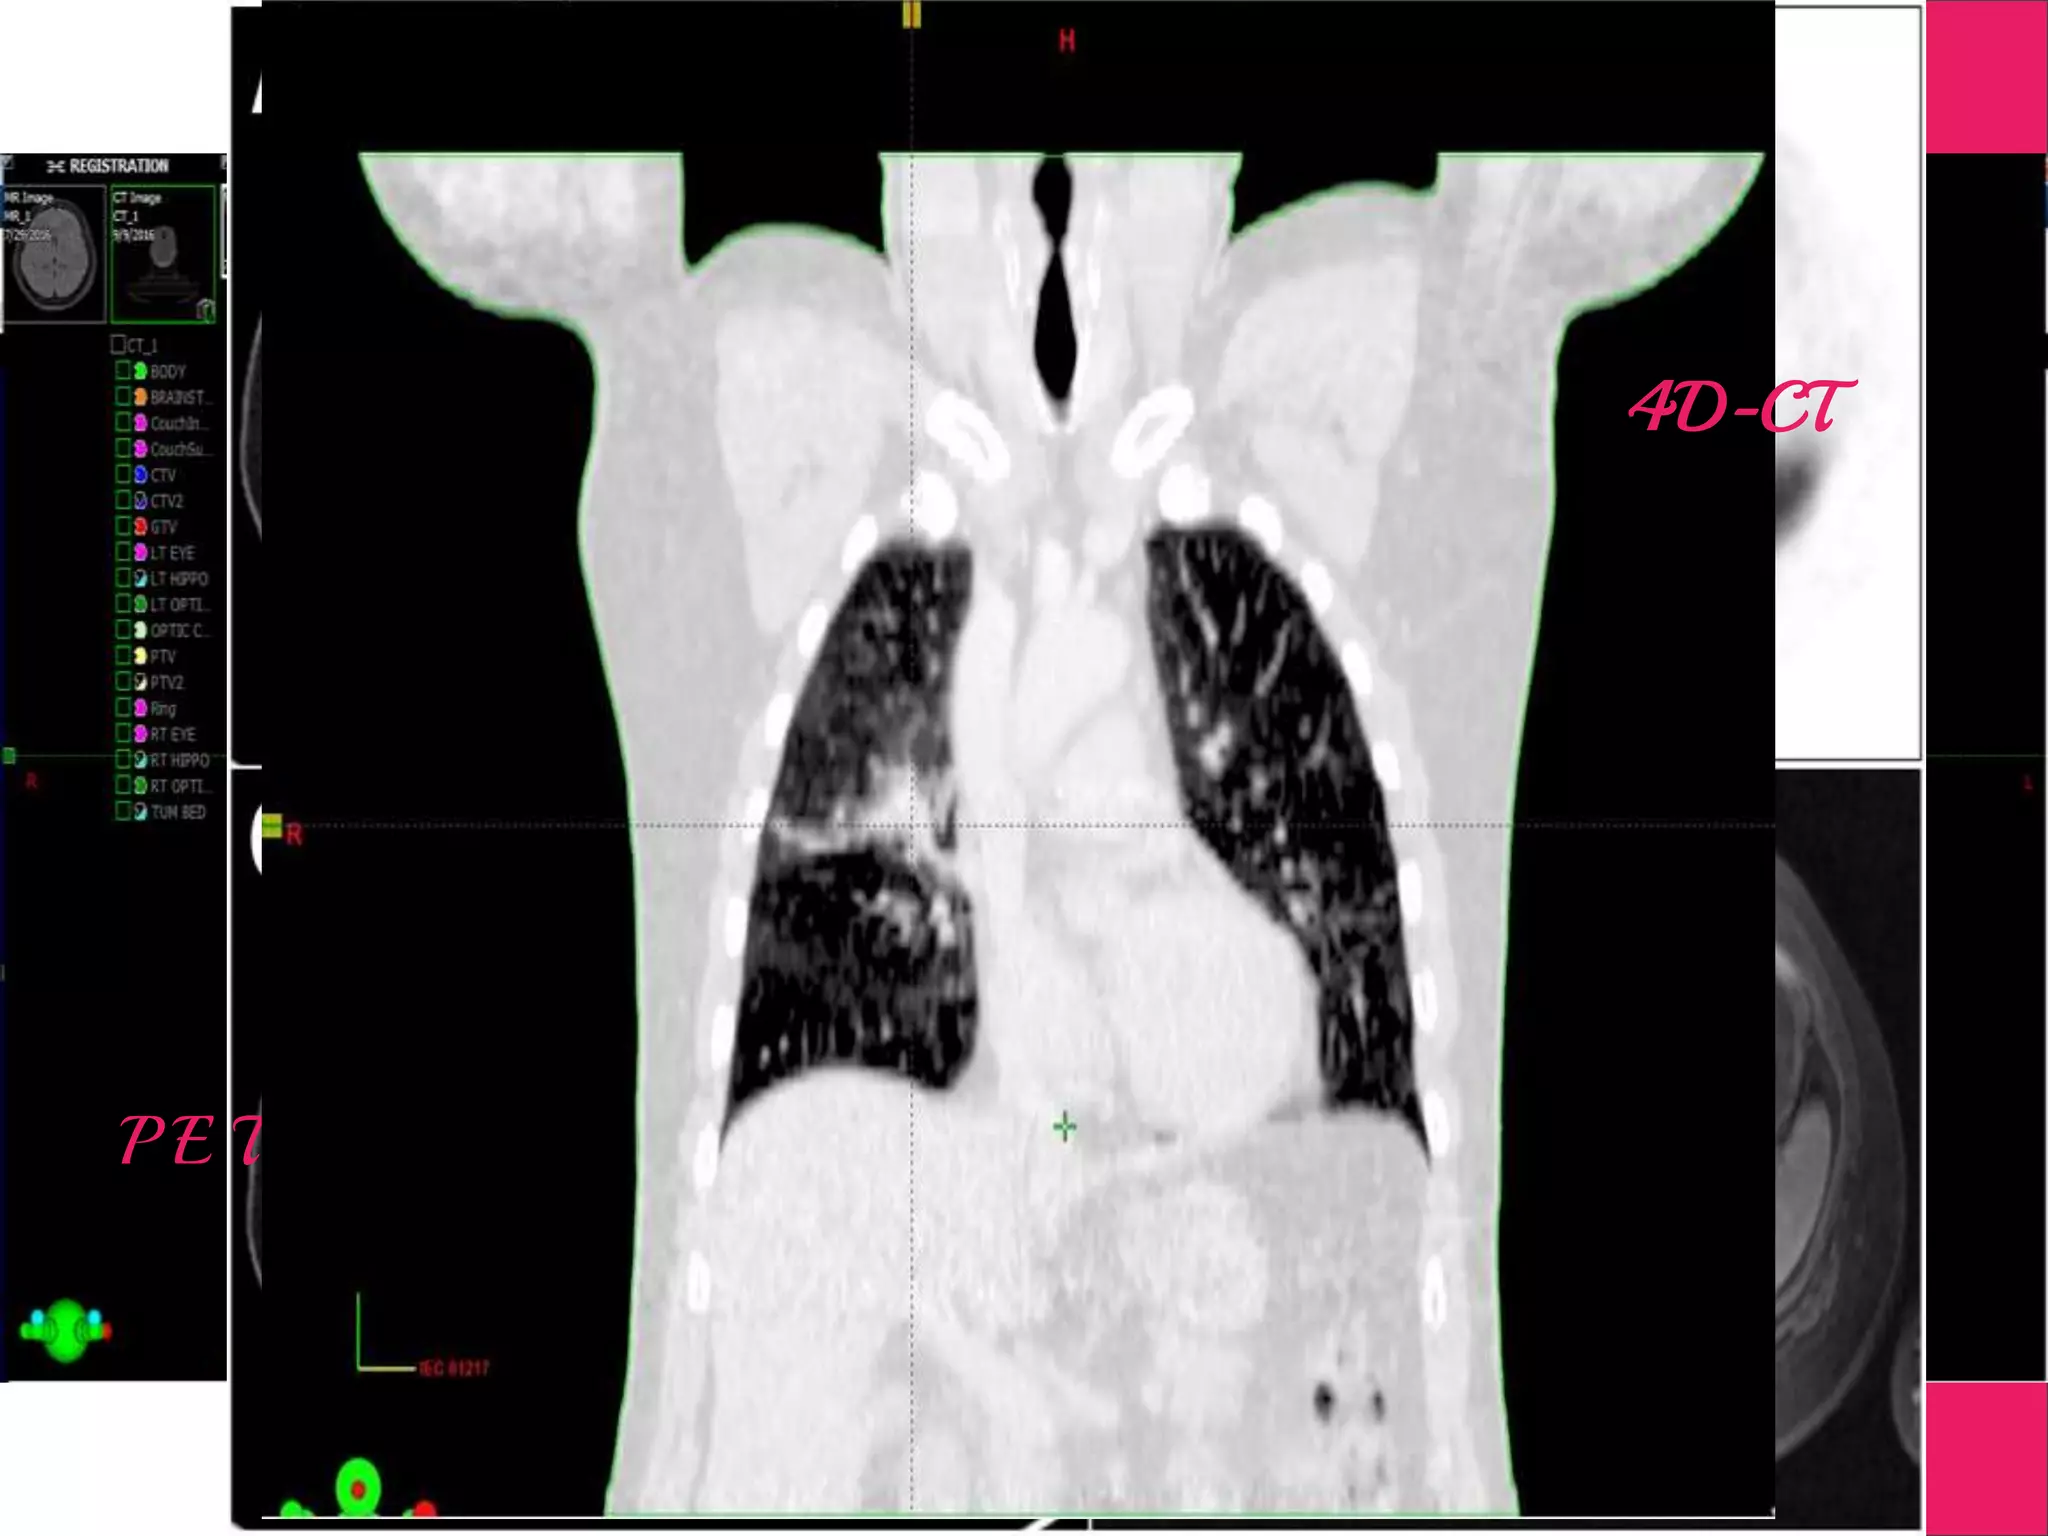

Supportive Images

Digitally Subtracted Angiograph

M R I

P E T

4D-CT

Supportive Images Digitally SubtractedAngiograph M R I P E T 4D-CT

Steps Involved inRadiotherapy Positioning of Patient Imaging in CT Treatment Planning Image Fusion Target Delineation MR, PET, DSA & 4DCT Plan EvaluationDosimetry Verification Image Guidance Treatment Delivery Patient